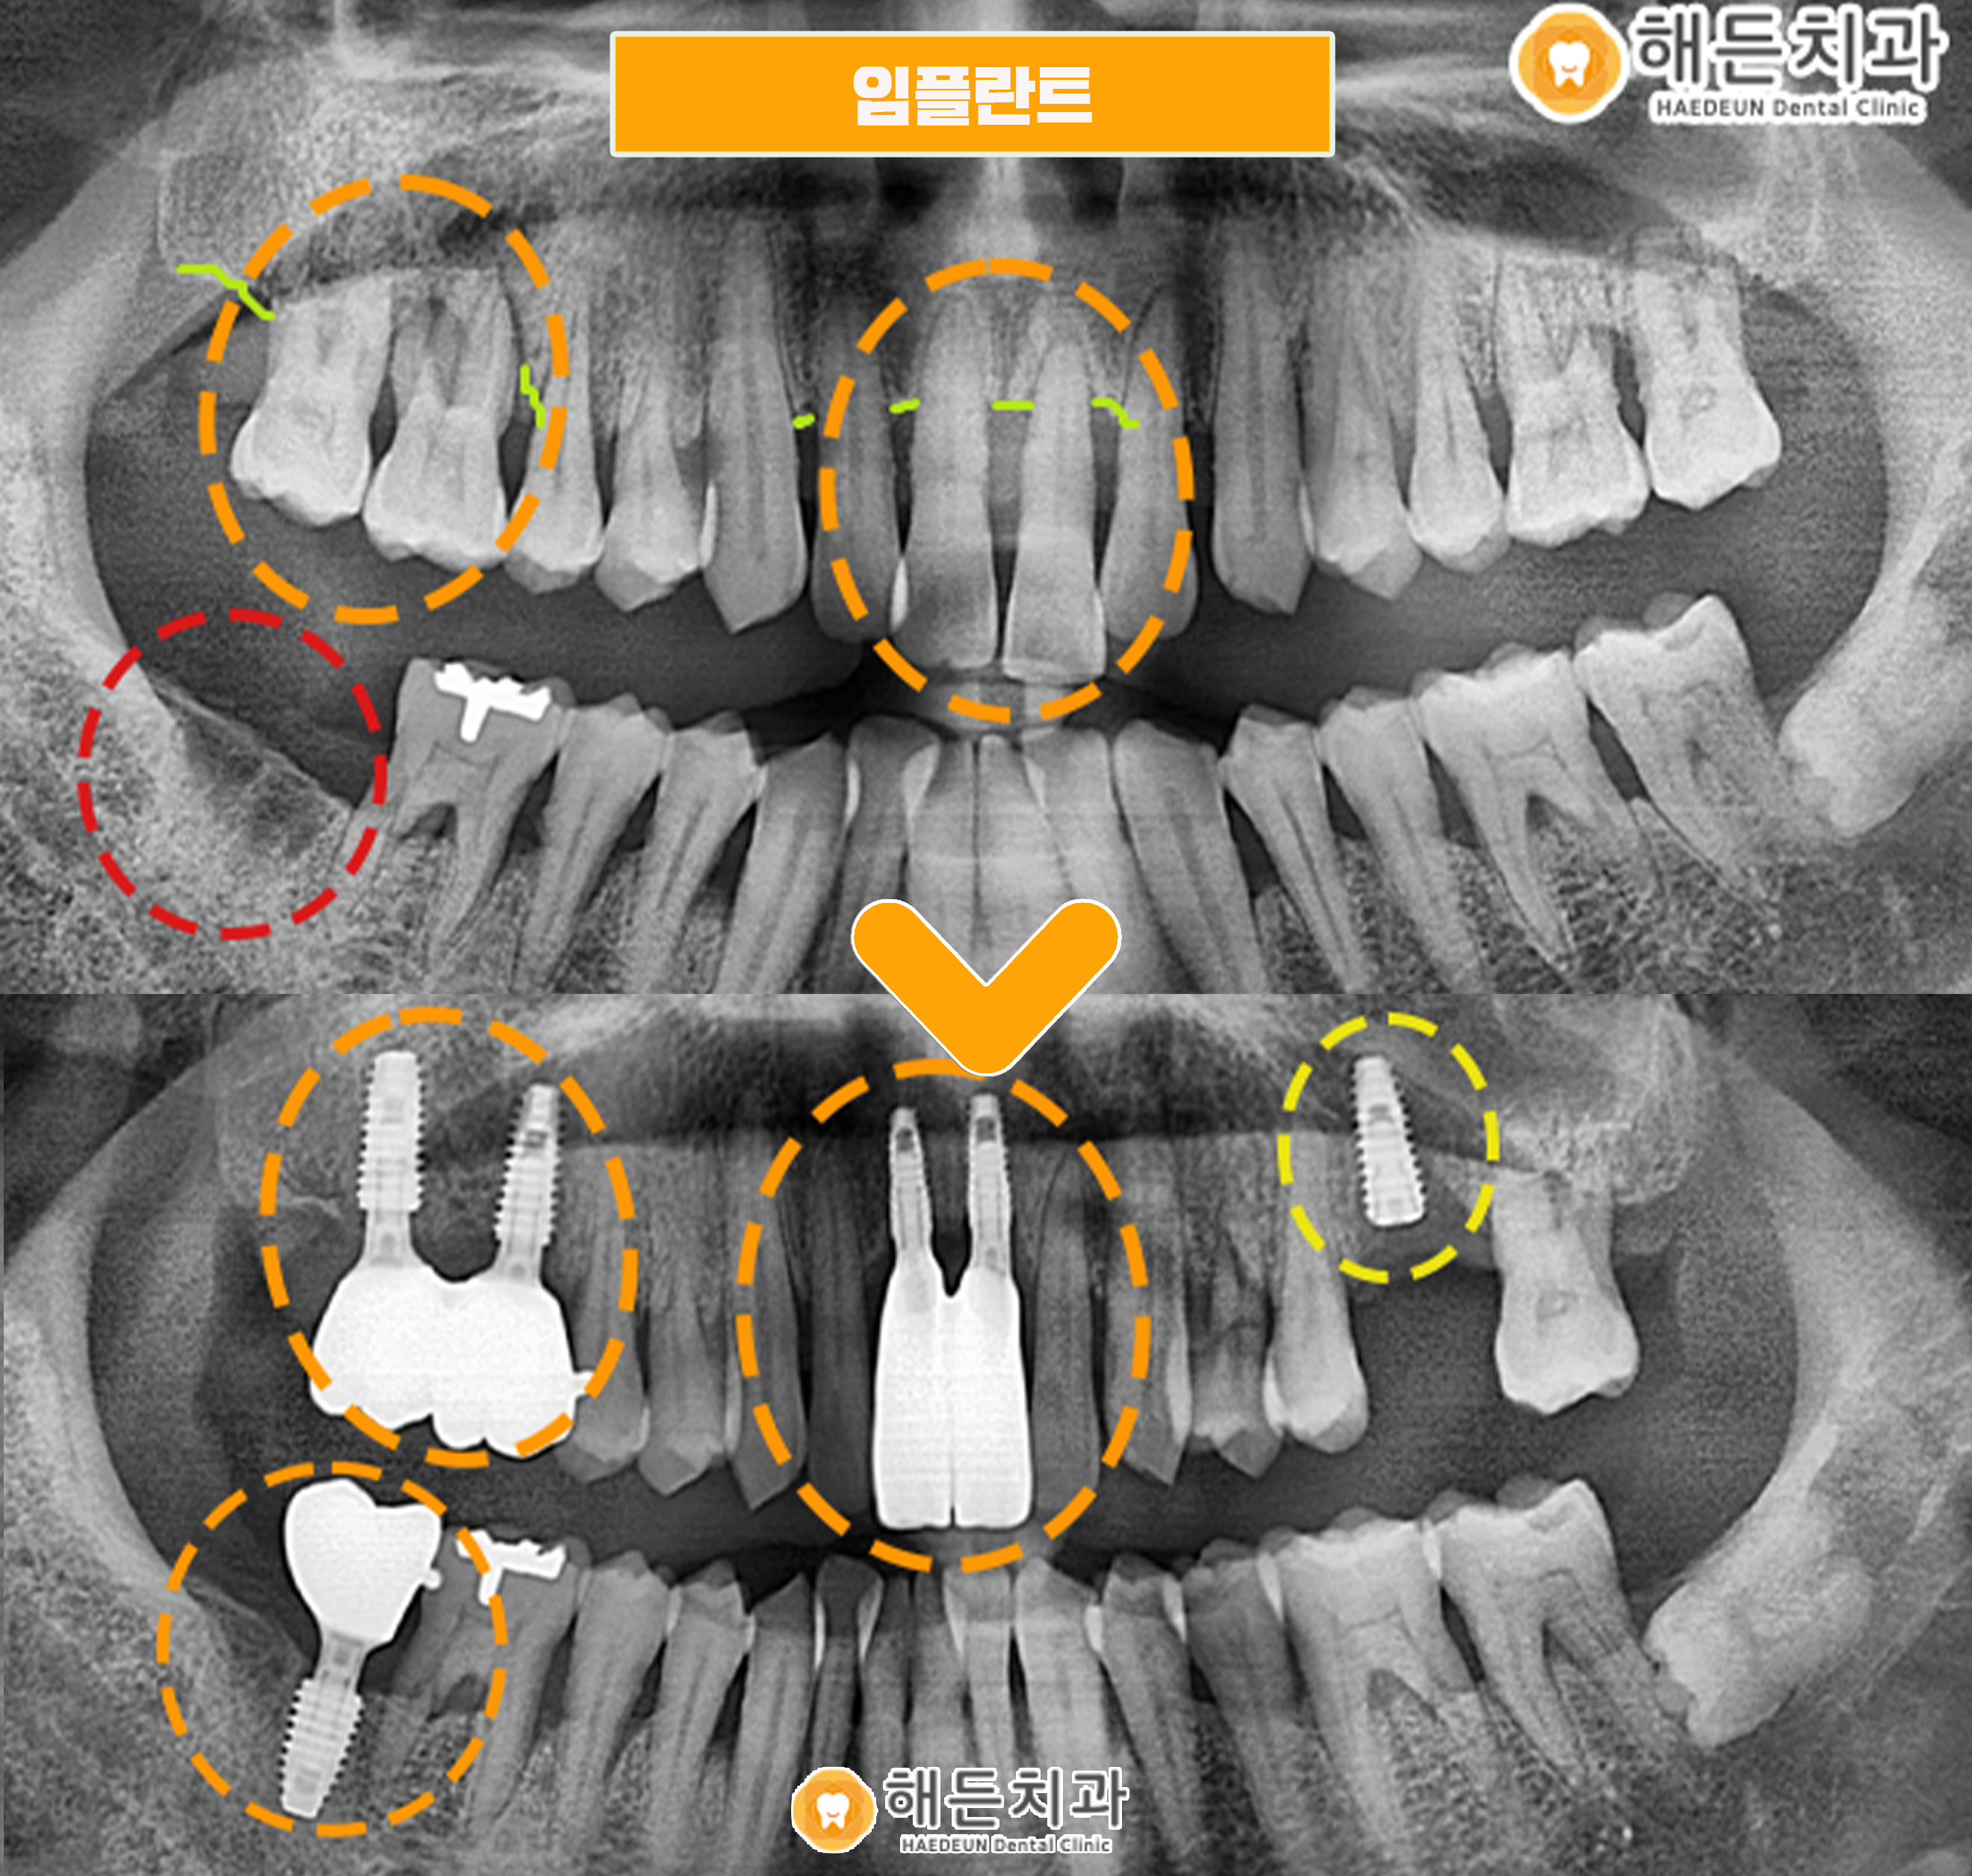

위 사진은 해든치과에 내원하신 조*수 님의 파노라마 사진입니다.

위의 환자분은 치주염이 심한 상태로 본원을 찾아주셨습니다.

파노라마 사진을 촬영해 검진해보니, 전체적으로 치주질환이 진행된 상태였으며

치주염으로 인해 잇몸 뼈 라인이 많이 내려가 있는 상태였으며, 흔들리는 치아도 다수였습니다.

전체적으로 치아 상태가 좋지 않아 치료가 필요한 치아가 많았지만,

우선적으로 상태가 가장 심각하고 환자분께서 불편감을 겪고 계신

오른쪽 위의 어금니2개와 위의 앞니2개를 발치하고 임플란트 식립을 진행하기로 했습니다.

뼈가 녹아 연두색 표시의 잇몸뼈 라인을 보시면, 잇몸라인이 치아 뿌리부분까지 내려앉은 상태로

치아가 거의 대롱대롱 매달려 있는 상황이었습니다.

더불어 기존에 상실되어있던 오른쪽 아래 빨간색 동그라미 표시의 두번째 큰 어금니 자리에도

임플란트 식립을 함께 진행하기로 했습니다.

배방역치과 해든치과에서의 임플란트 식립 후 사진입니다.

현재 위의 파노라마 사진을 보시면 임플란트 픽스처만 식립되어 있는 상태인데요.